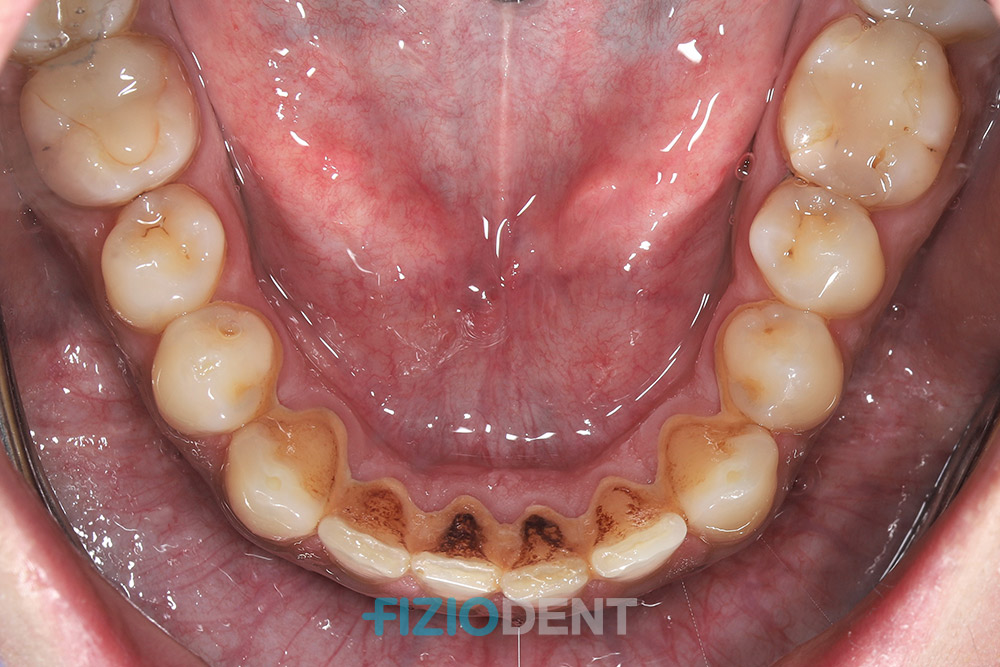

Gingivitis is the inflammation of the gums (gingiva). Symptoms include bleeding gums and changes in gum color. Healthy gums are light pink and often have a texture resembling the surface of an orange peel, while inflamed gums are typically red and swollen.At the stage of gingivitis, there is no loss of the supporting structures of the teeth, and the condition can be fully treated. Treatment involves professional dental cleaning and enhanced oral hygiene at home.

After tooth decay, periodontitis is one of humans' most common infectious diseases. It is a condition characterized by the loss of the supporting structures of the teeth. Because pain from periodontitis usually occurs only in the advanced stages of the disease, many patients are unaware they have it, which is why regular dental check-ups are so important. If you notice symptoms such as bleeding gums, bad breath, or loose teeth, it is essential to undergo a periodontal examination to prevent the disease from progressing. Treatment for periodontitis begins with initial therapy, which includes scaling and root planing (a combination of manual and ultrasonic techniques) under local anesthesia. This is followed by the supportive phase, which involves regular check-ups and cleaning of newly formed deposits. During this phase, the patient’s responsibility and discipline in attending follow-ups and maintaining good oral hygiene are crucial.